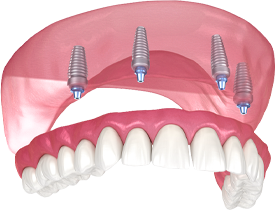

По уникальной методике

БЕЗ отёков и надрезов

Установка

за 1 день